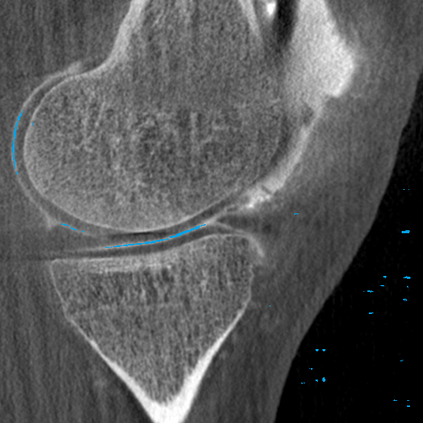

Analyzing knee cartilage thickness and strain under load can help to further the understanding of the effects of diseases like Osteoarthritis. A precise segmentation of the cartilage is a necessary prerequisite for this analysis. This segmentation task has mainly been addressed in Magnetic Resonance Imaging, and was rarely investigated on contrast-enhanced Computed Tomography, where contrast agent visualizes the border between femoral and tibial cartilage. To overcome the main drawback of manual segmentation, namely its high time investment, we propose to use a 3D Convolutional Neural Network for this task. The presented architecture consists of a V-Net with SeLu activation, and a Tversky loss function. Due to the high imbalance between very few cartilage pixels and many background pixels, a high false positive rate is to be expected. To reduce this rate, the two largest segmented point clouds are extracted using a connected component analysis, since they most likely represent the medial and lateral tibial cartilage surfaces. The resulting segmentations are compared to manual segmentations, and achieve on average a recall of 0.69, which confirms the feasibility of this approach.